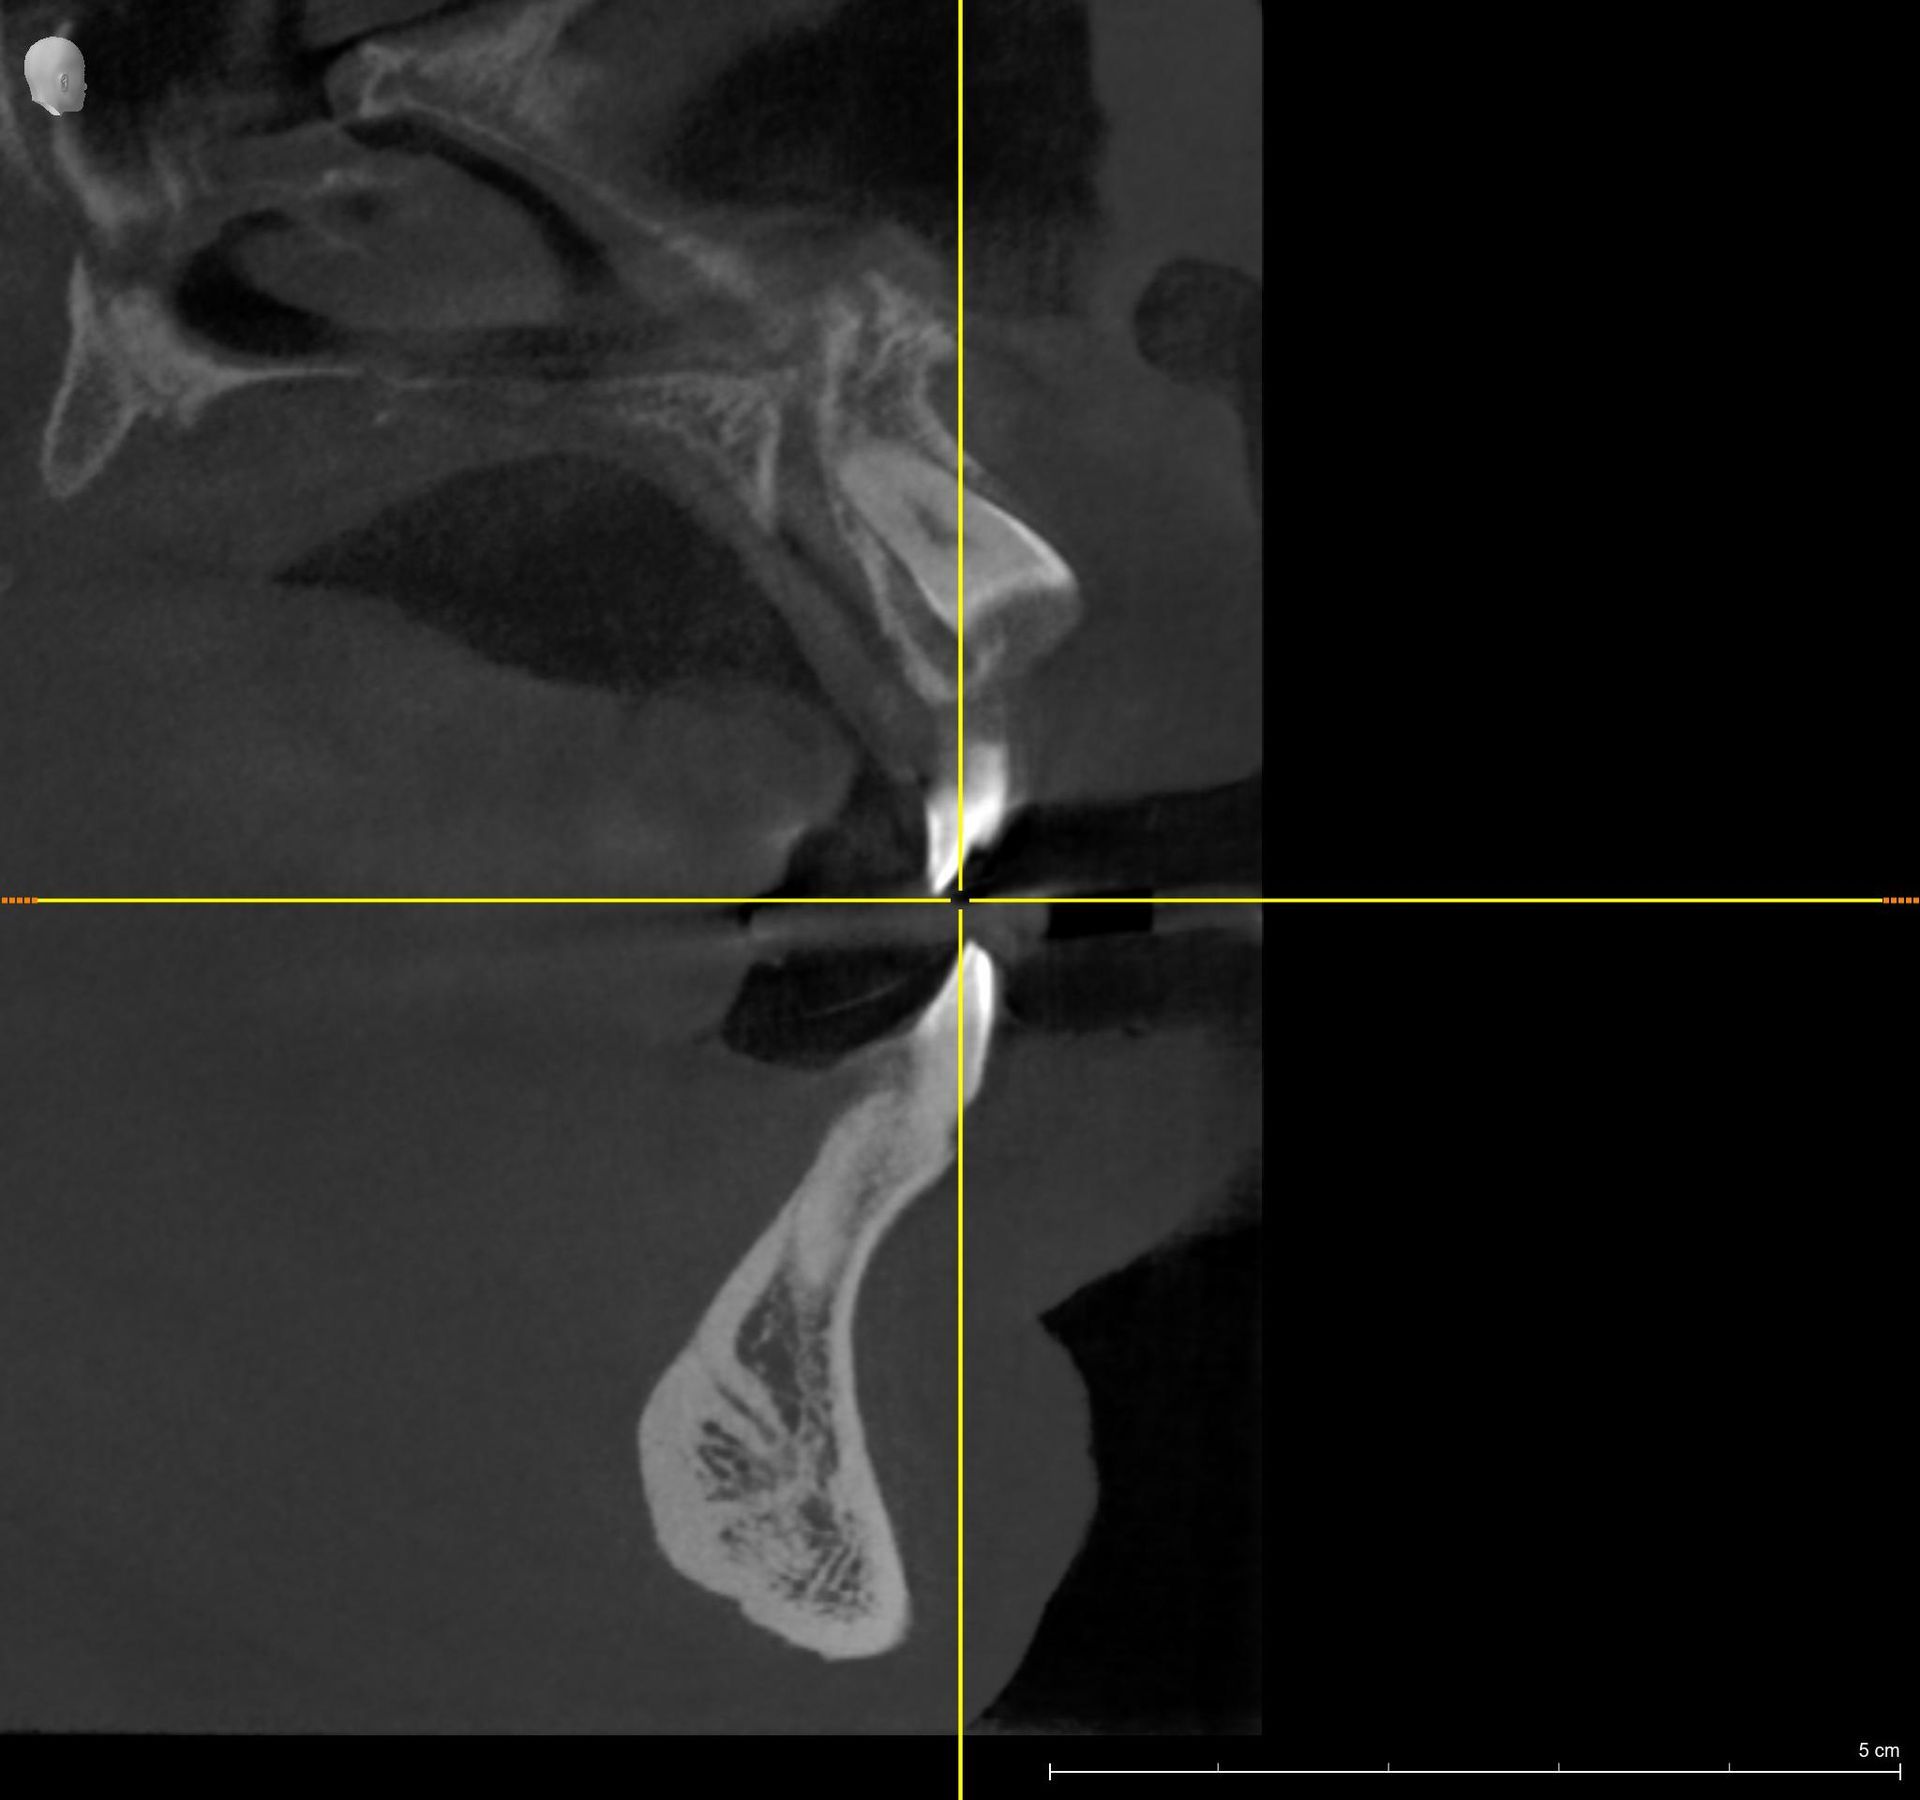

La nostra struttura utilizza un’apparecchiatura radiologica di ultima generazione (Sirona Orthophos SL 3 D), che permette, in un’unica soluzione, di effettuare esami di arcate dentarie, cefalometrici e volumetrici 3 D).

Il nuovo sensore, a conversione diretta, garantisce precisione, con immagini più nitide, dettagliate e a bassissima emissione di raggi X (da 5 a 20 volte inferiore rispetto alla TC tradizionale); con bassissima dose per il paziente; quindi molto adatta ai pazienti più piccoli.